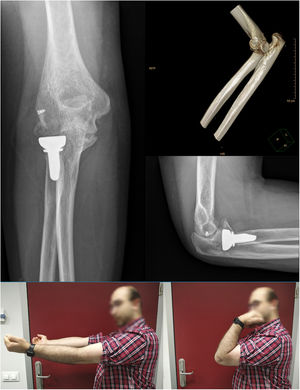

As complications in addition to the abovementioned case (case 2) who presented with stiffness, case 3 showed grade II heterotopic ossification at five months follow-up without clinical significance (Image 4). Residual instability, joint incongruity, infection, complicated haematoma, material breakage or neurovascular injury were not identified in any of the cases during follow-up. In sum, the motion values prior to removal of the IJS-E, type of reintervention and functional values are shown in Table 2.

This case series presents the introduction of the IJS-E device into our surgical protocol for the treatment of persistent acute complex instability of the elbow despite successful osteoligamentous repair as a potentially valid alternative to external fixation. The mean follow-up of our five patients was 9.8 months, with a final arc of motion of 122° flexion-extension with full pronosupination. The DASH and MEP scales averaged a score of 11.78 and 94 points, respectively, which translates into an excellent final functional outcome. In all cases, adequate joint congruence was achieved, allowing immediate and early initiation of active postoperative mobilisation. However, when assessing the results obtained, we must consider that a MUA was performed in all cases, coinciding with the scheduled removal of the device.